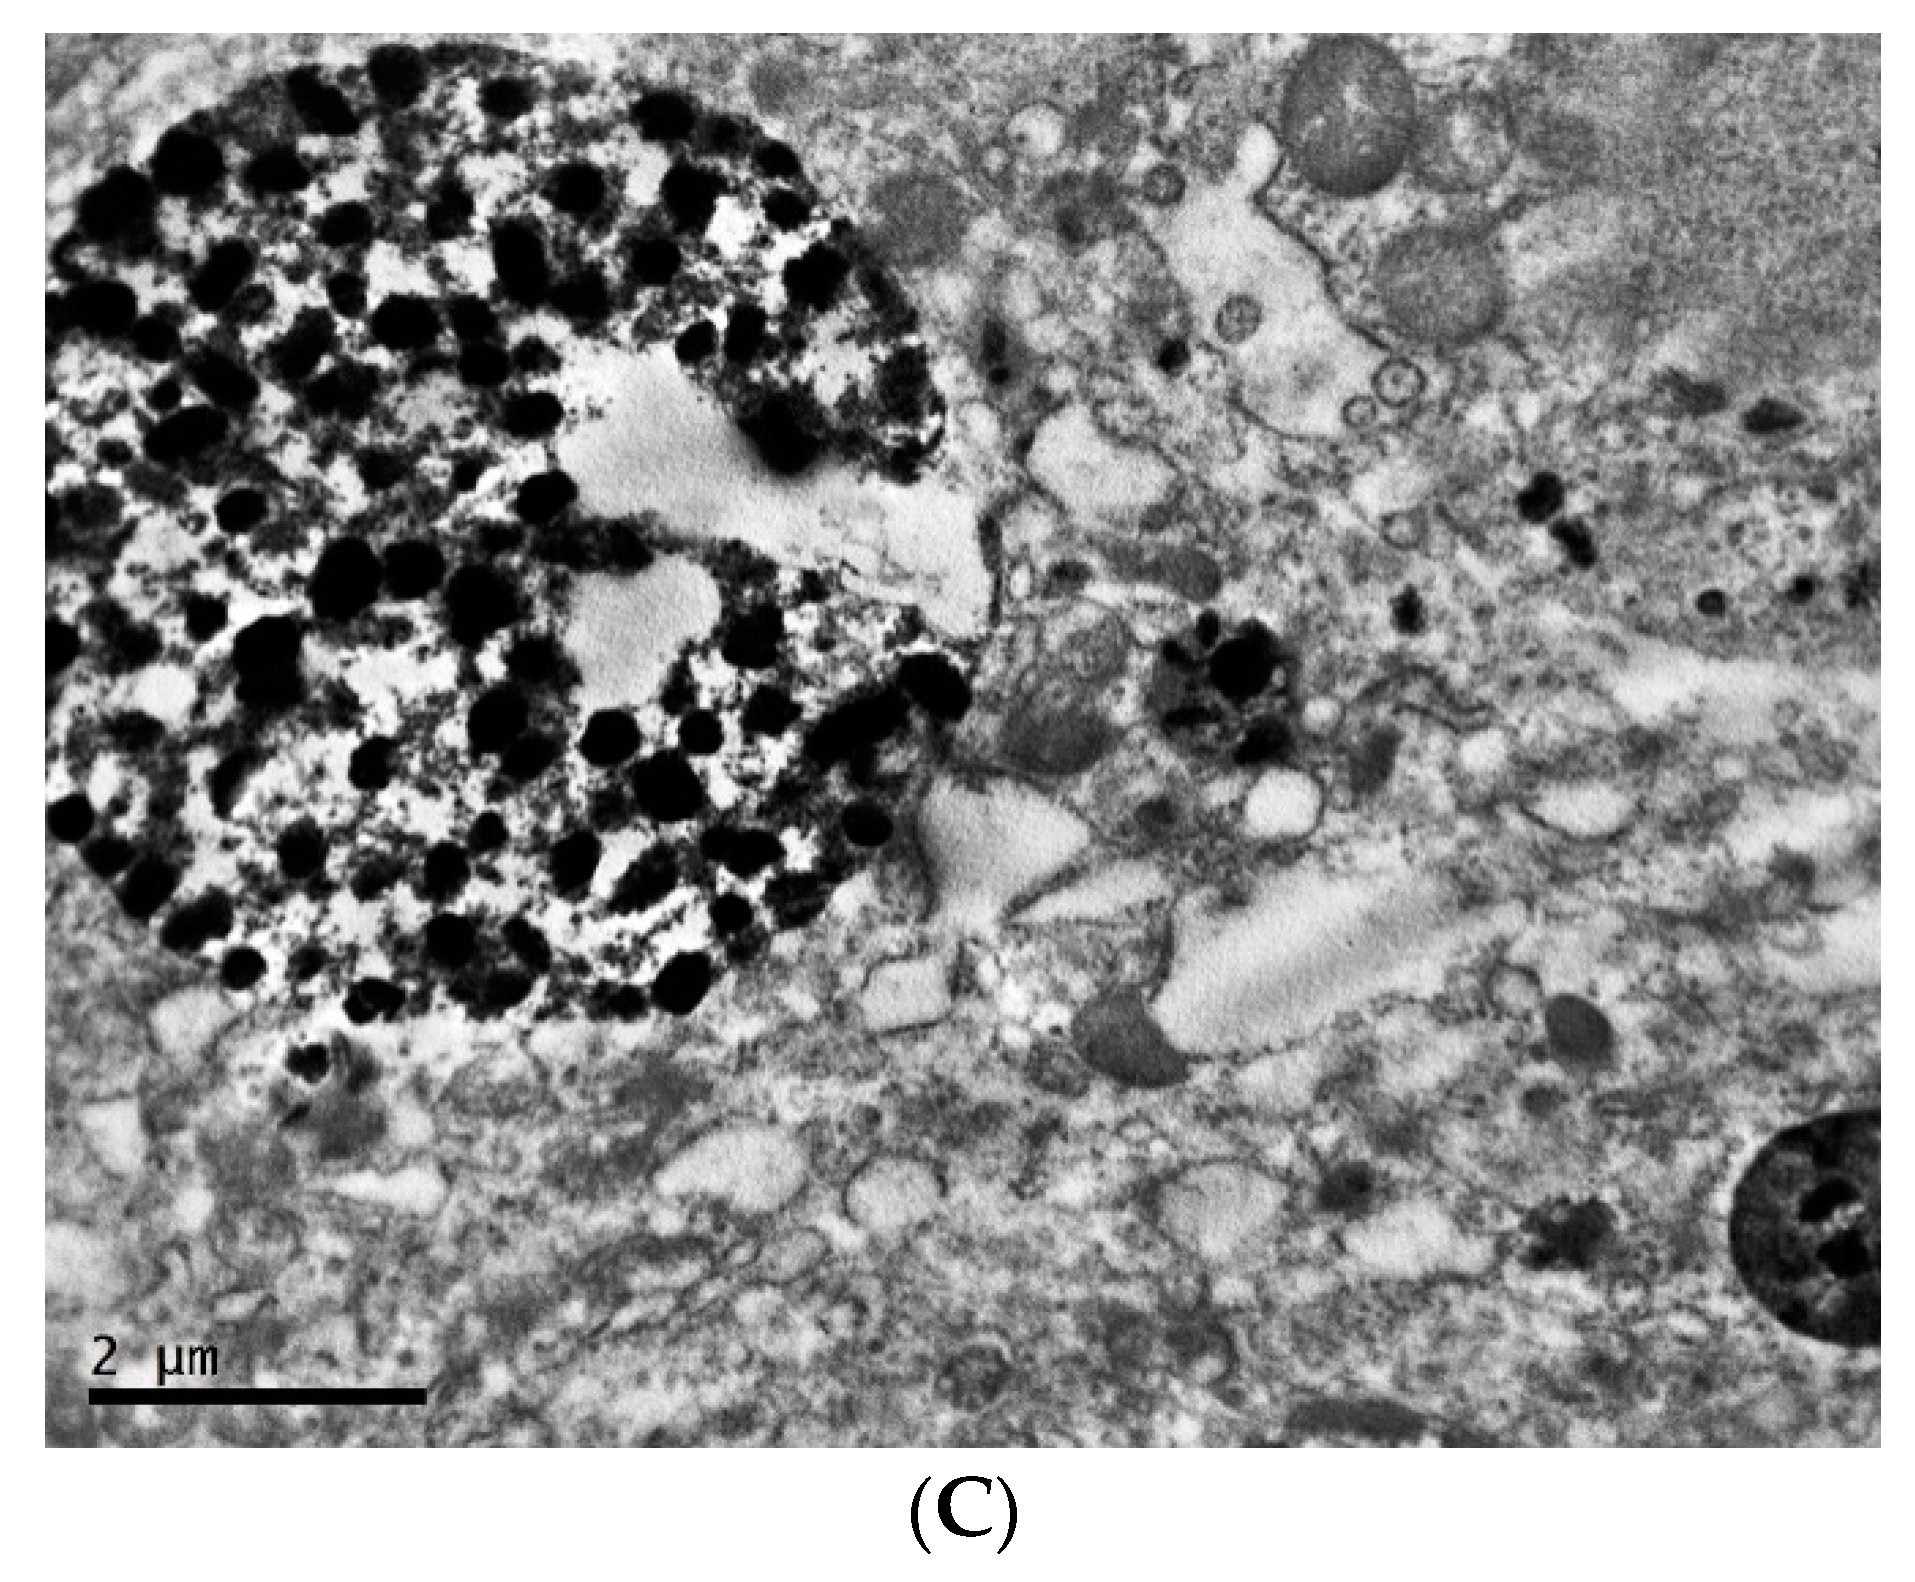

2.2. Ultrastructure of Transplantable Malignant Melanoma B16 in Conditions of Constant Lighting Regime